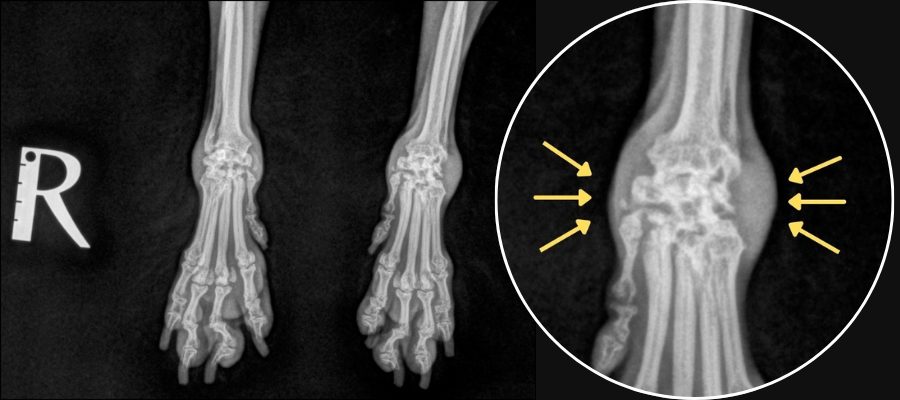

<手根関節のレントゲン>

【健常】

【関節リウマチ】

自己免疫の異常によって自分の関節を攻撃してしまう疾患です。免疫介在性関節炎に含まれ、多数ある免疫介在性関節炎のうち、びらん性関節炎に分類されます。びらん性とはレントゲン検査で骨びらん(骨の虫食い様の不連続像)が認められることを指します。 主な症状は、関節の腫れ、足を痛がるなどの症状です。日によって、または時間によって痛がる足が変わることがあります。重症例では関節が壊れることにより、かかとや手首がベタっと地面についてしまいます(いわゆるベタ足)。また、関節症状以外にも発熱、食欲不振などの全身症状も見られることがあります。